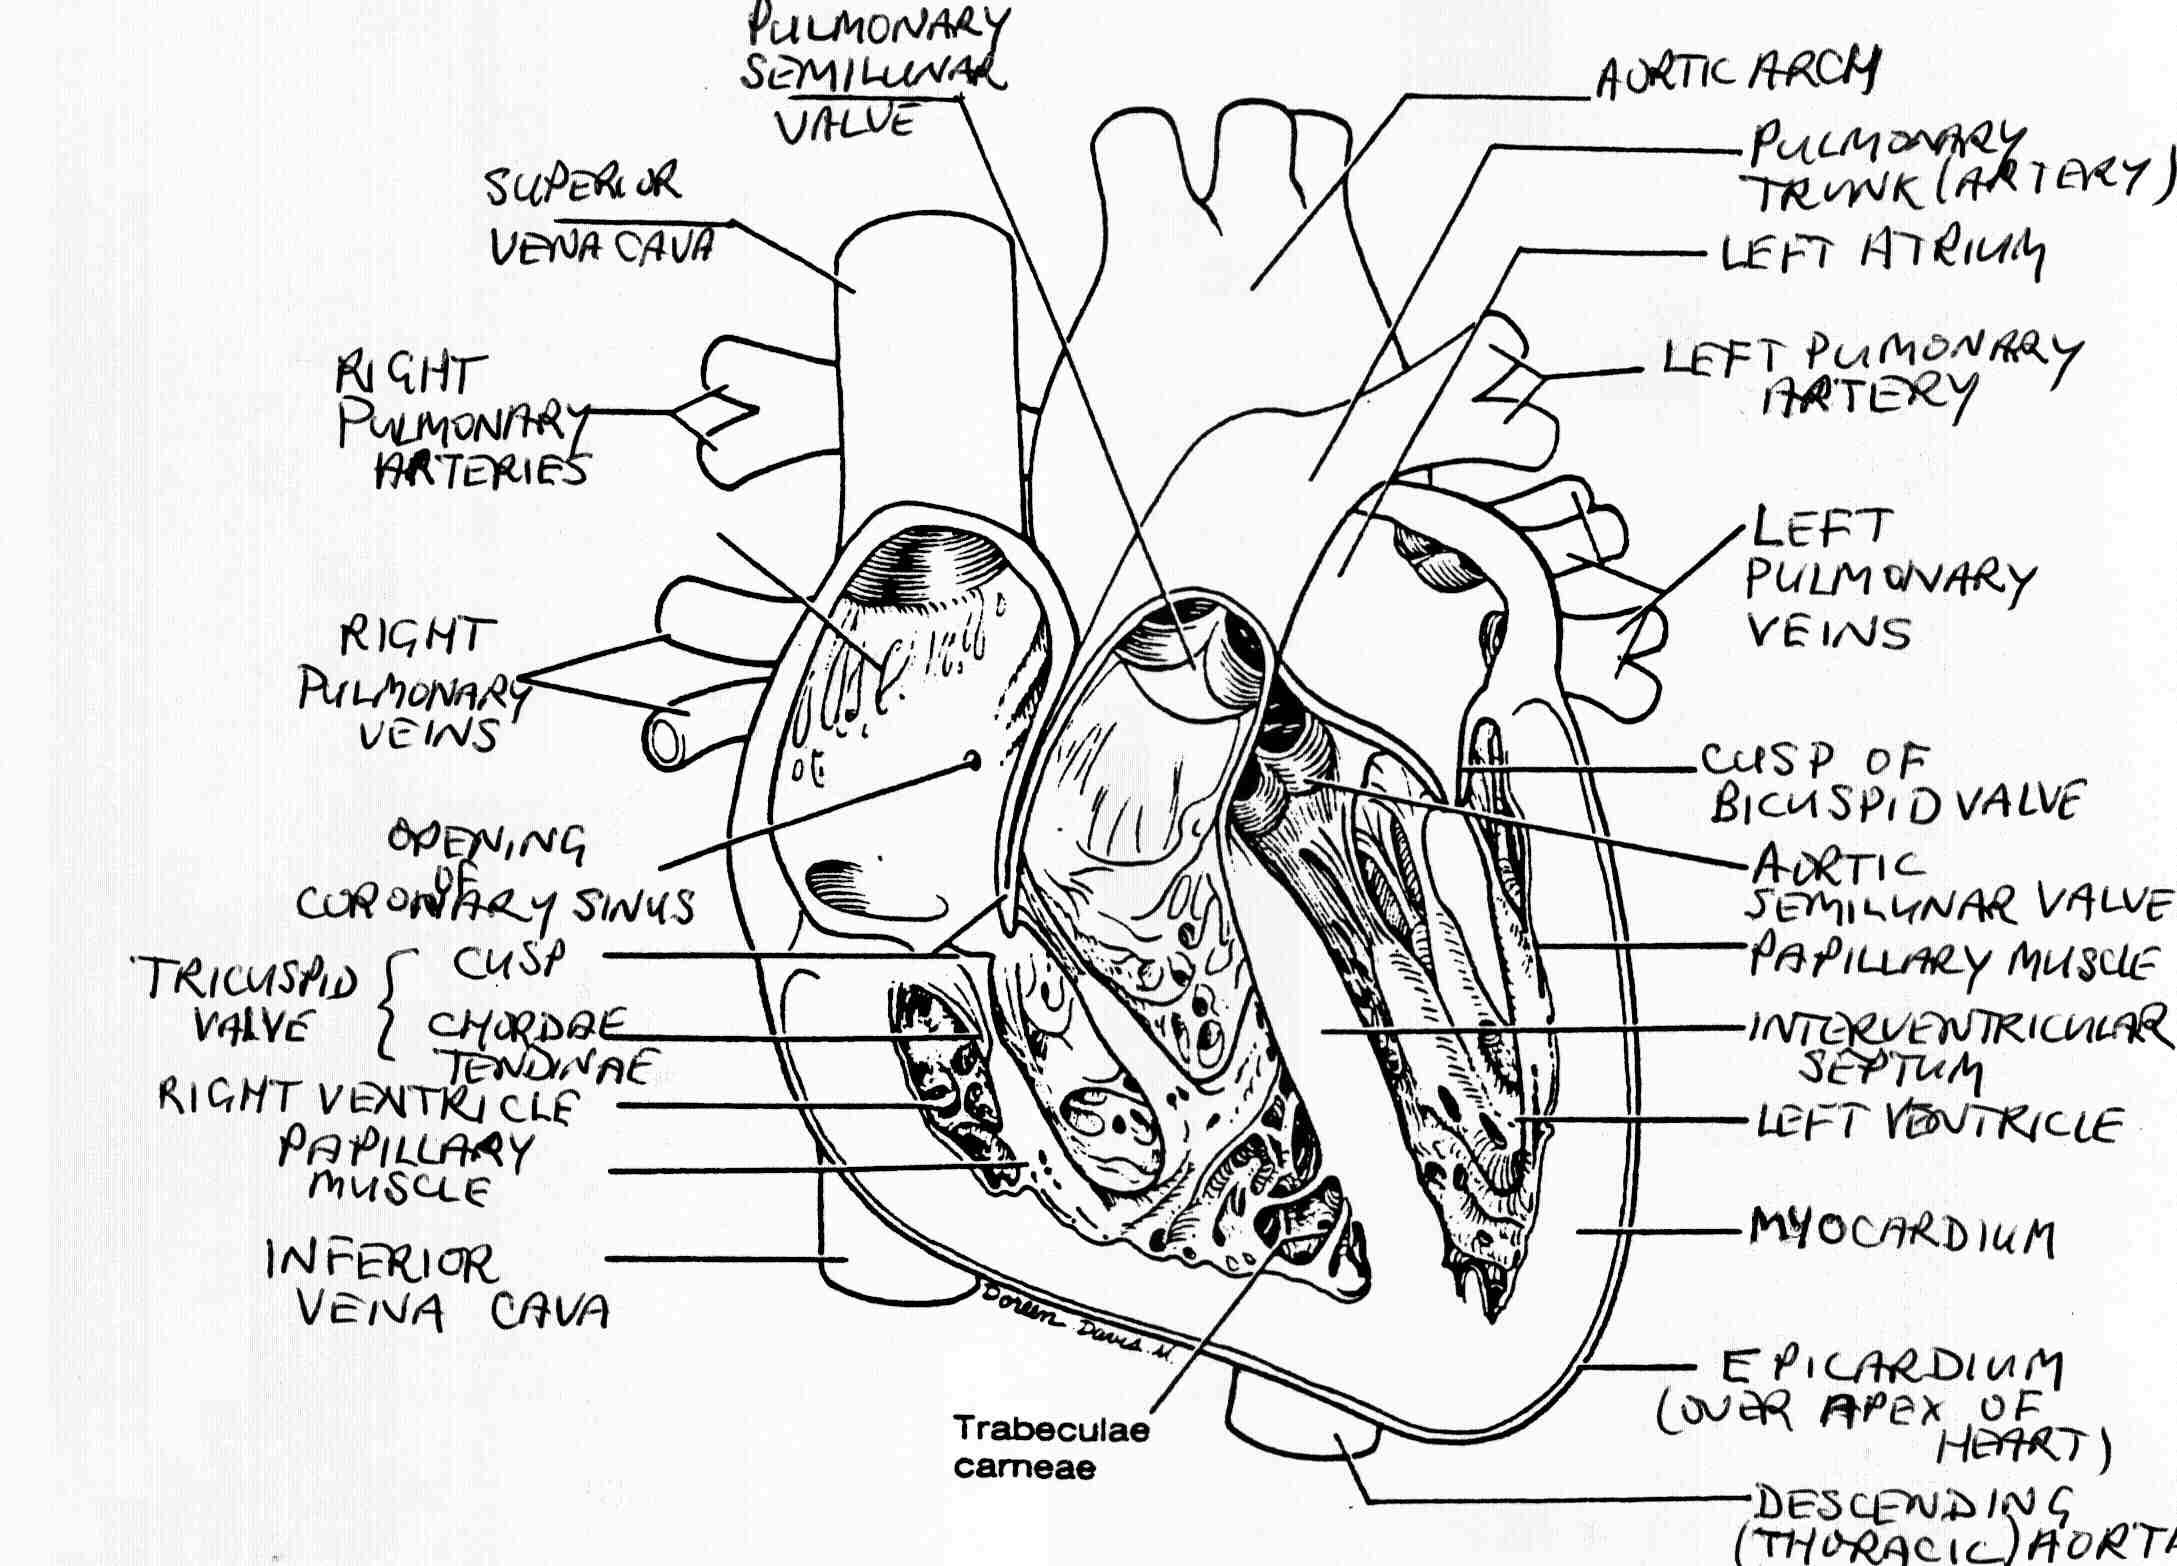

What are the parts that make up a human heart? Diagrams and More | Human heart diagram, Heart

What are the parts that make up a human heart? Diagrams and More | Human heart diagram, Heart  Human heart by kortney16 on DeviantArt

Human heart by kortney16 on DeviantArt  Human Heart-Gross structure and Anatomy - Online Biology Notes

Human Heart-Gross structure and Anatomy - Online Biology Notes  Personal Blogs: This mini size heart is also

Collection of Human heart clipart | Free download best Human heart clipart on ClipArtMag.com  15 Diagram Of Heart In Human Body | Robhosking Diagram

15 Diagram Of Heart In Human Body | Robhosking Diagram  How to Draw a Human Heart: 5 Steps (with Pictures) - wikiHow

Health Care: Human Heart Anatomy Pics  Gross Anatomy Of The Human Heart Digital Art by Stocktrek Images

43+ Human Heart Handmade Diagram PNG | Diagram of Everythings  Human Heart Diagram Without Labels - koibana.info | Human heart diagram, Heart diagram, Human

Human Heart Diagram Without Labels - koibana.info | Human heart diagram, Heart diagram, Human  Human Heart Diagrams | 101 Diagrams

Human Heart Diagrams | 101 Diagrams  Human Heart Simple Drawing at GetDrawings | Free download

Anatomy of the Heart: Physiology | Health Life Media  Human Heart Anatomy Drawing at GetDrawings | Free download

Human Heart - Circulatory System | OER Commons  de Location Of Human Heart In Body mar webmds heart anatomy page provides a detailed image of

Scientific medical illustration of parts of the human heart 685453 Vector Art at Vecteezy  Human Heart Drawing Outline at GetDrawings | Free download

Anatomy of the human heart  Human Heart Drawing Line Work stock vector art 481404348 | iStock